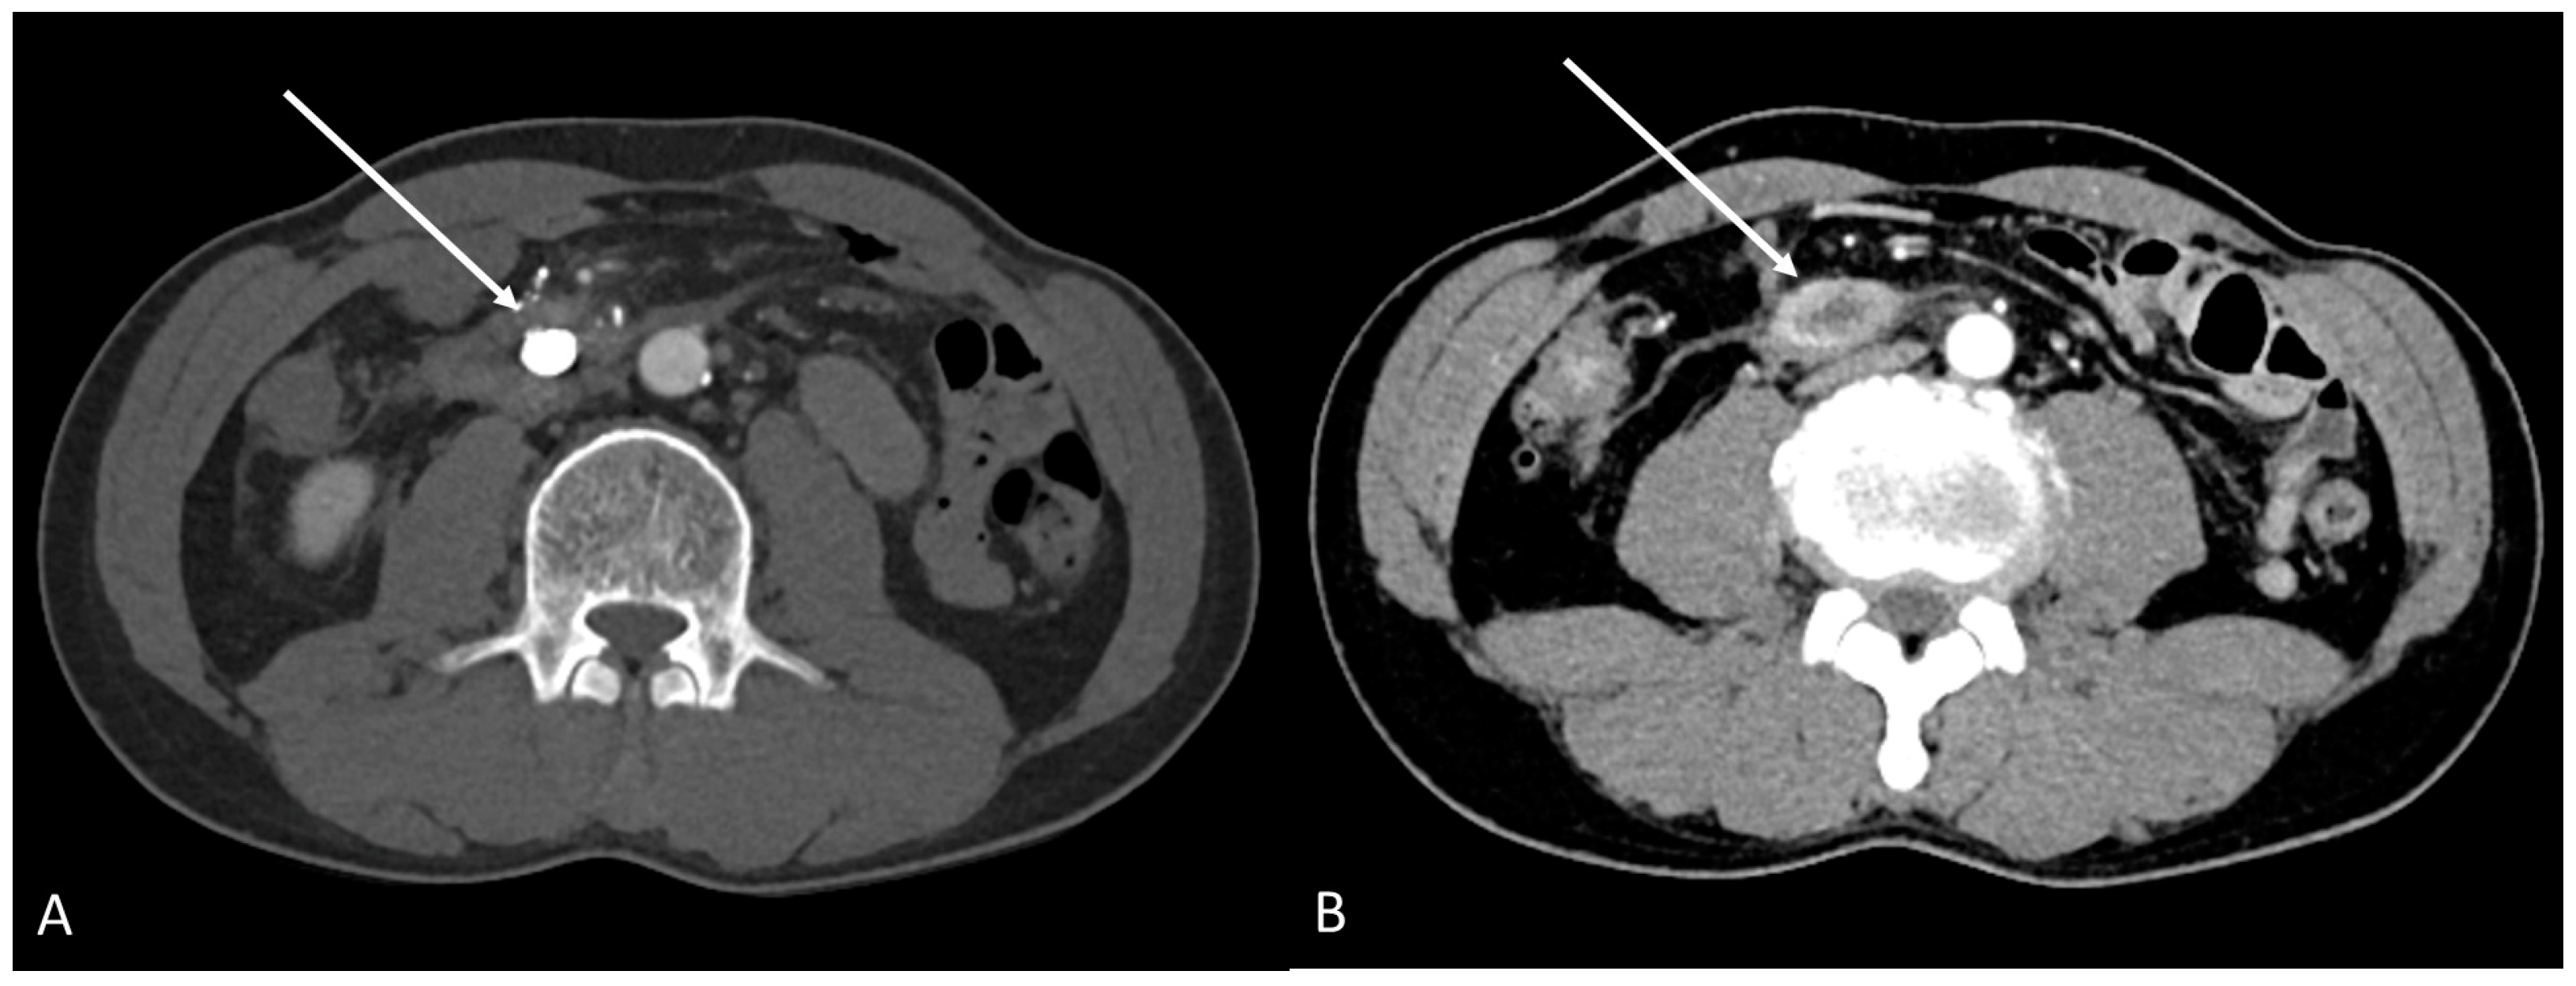

2. Case Report